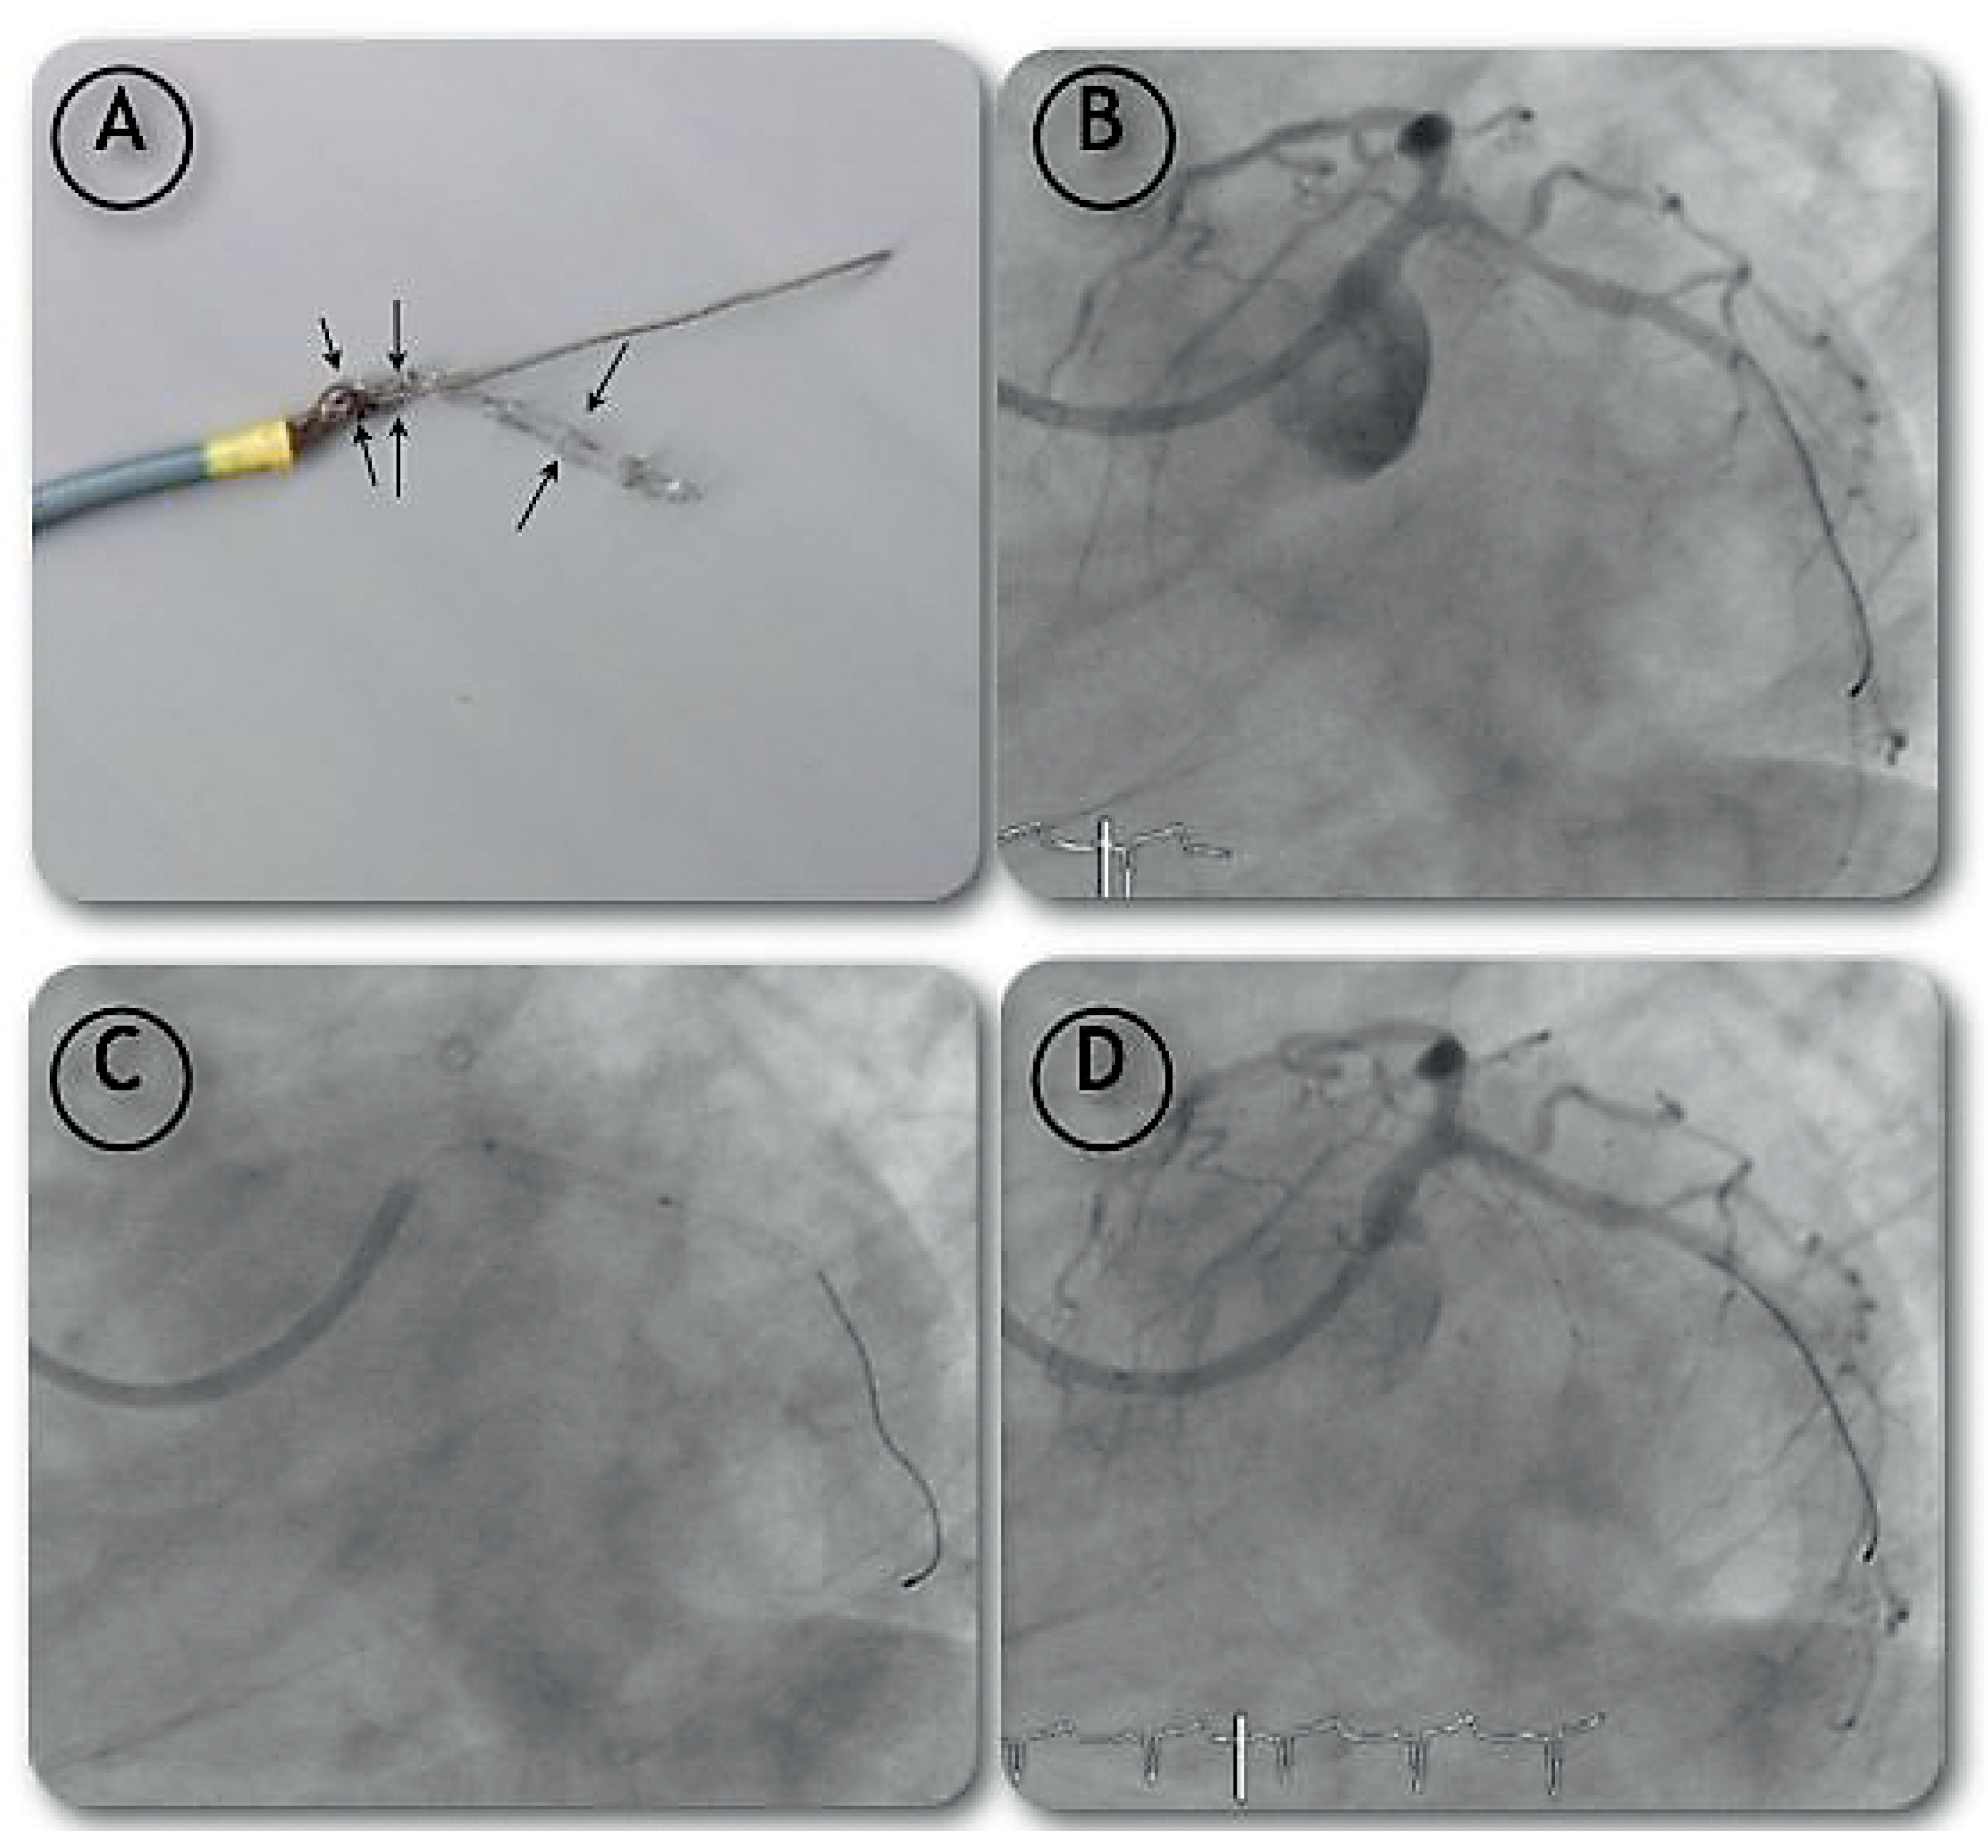

Case report